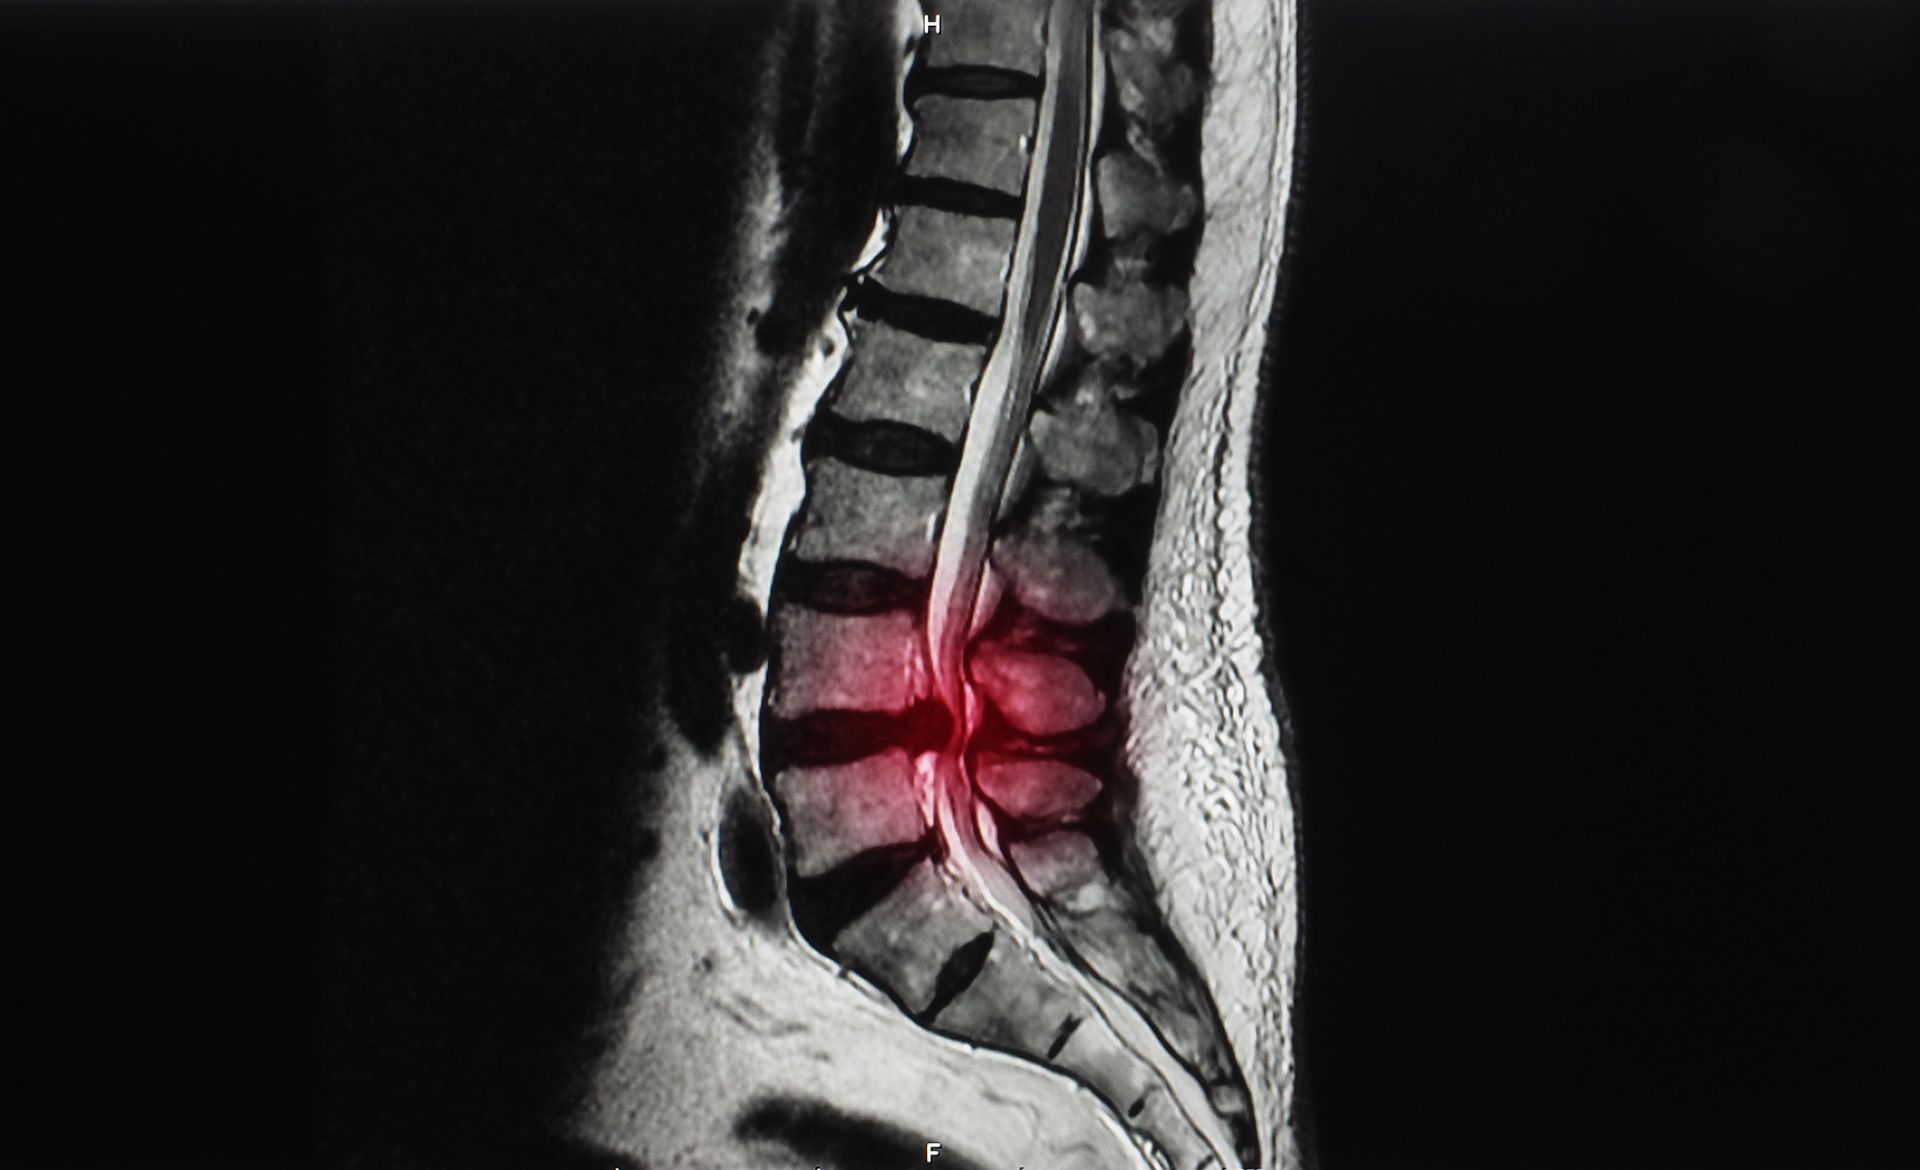

- Imaging: MRI scans, CT scans, and X-rays are used to pinpoint the source and extent of compression.